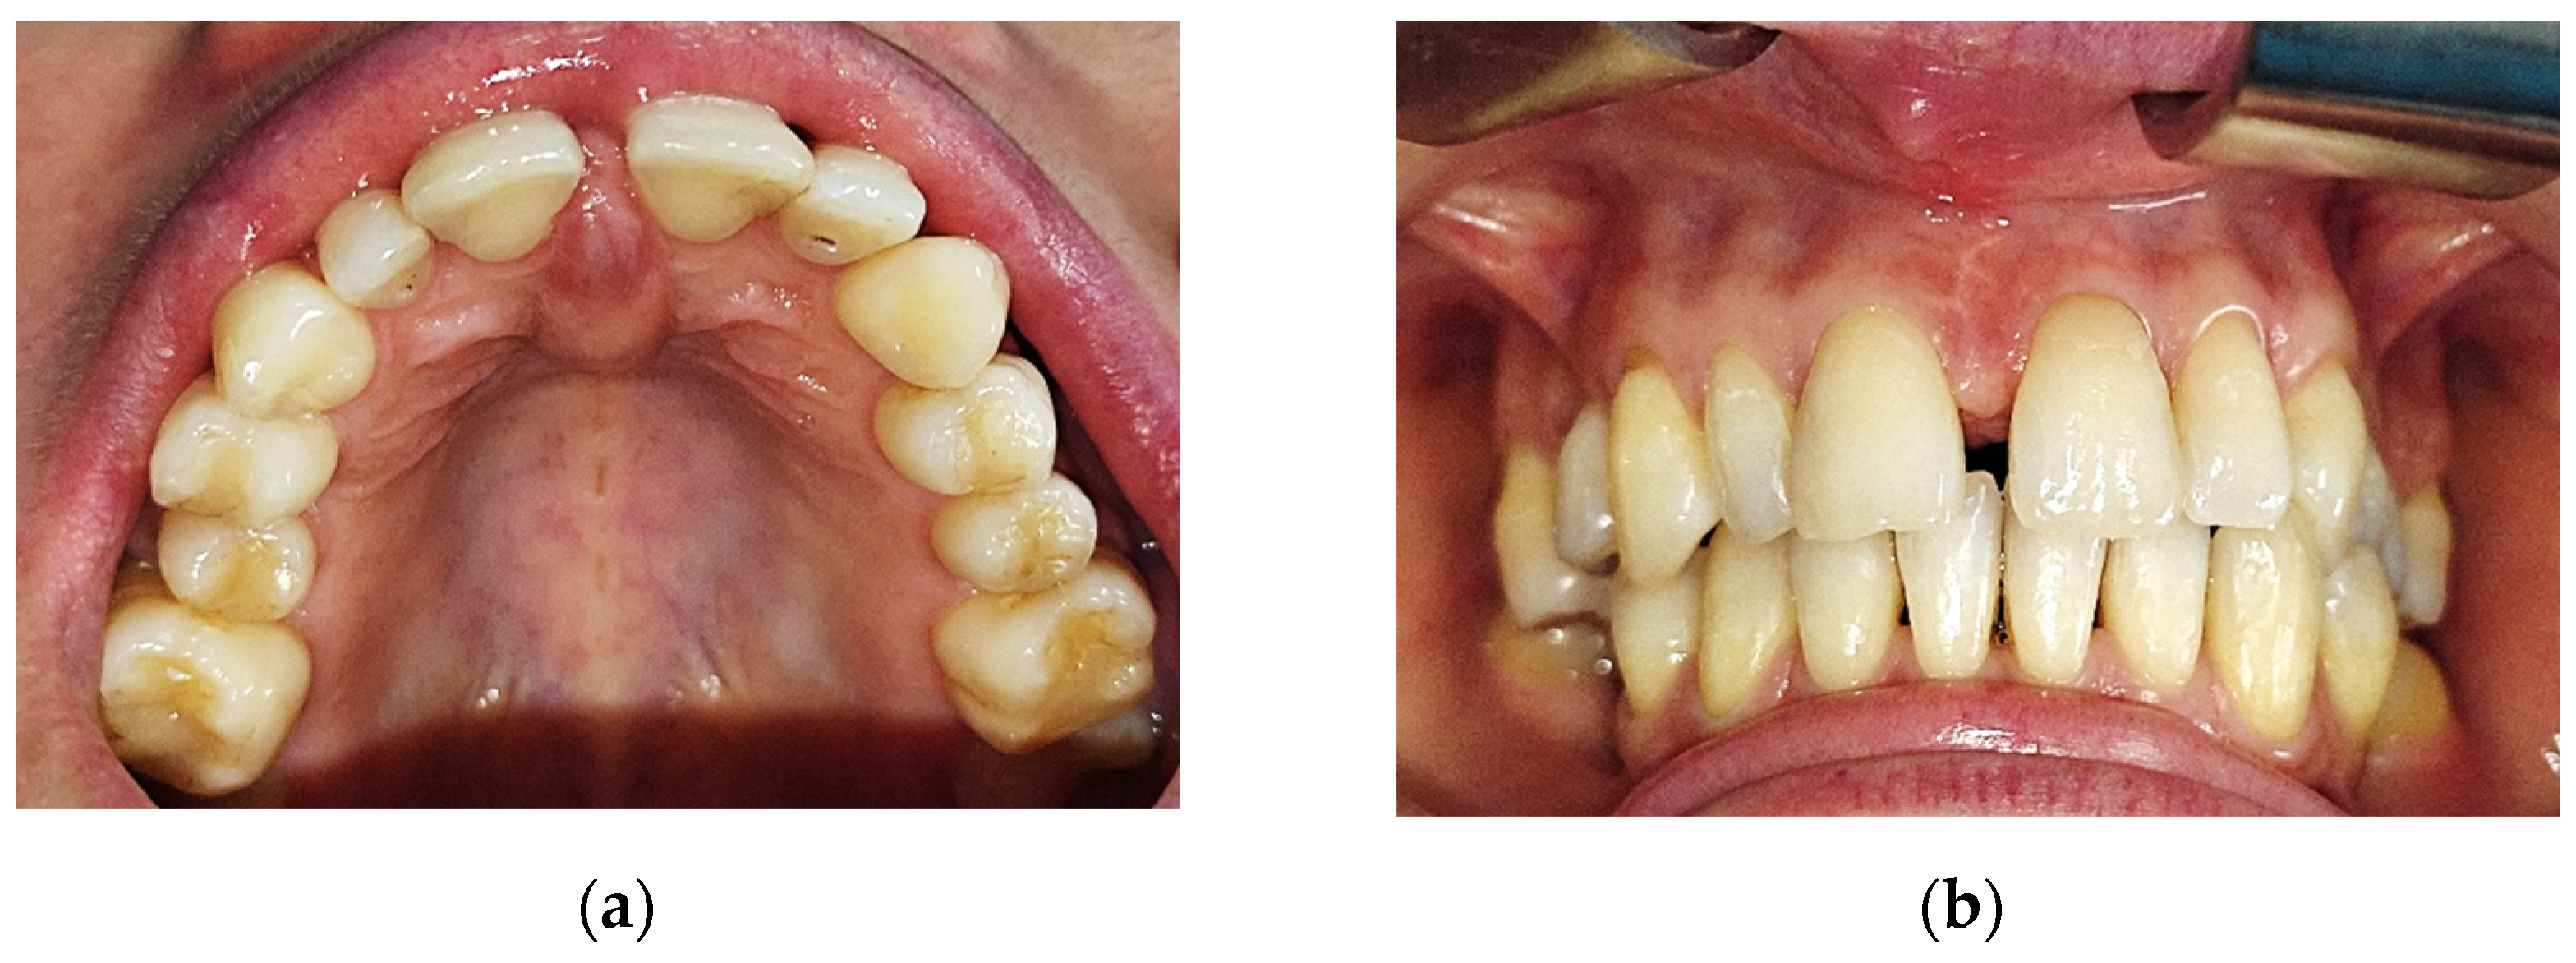

At the clinical exam, the lesion had a shape of a droplet, well delimited, with a dimension of approximately 15 mm (sagittal plane)/10 mm (transverse plane), with a nodular lower pole located at the median palatal fibromucosa, extended between the bilateral palatal rugae. It had a pink tint, smooth surface and soft, resilient and depressible consistency. The upper pole of the lesion was located interdentally between the superior central incisors (1.1–2.1, using the FDI Dental Numbering System, or 8–9, using the Universal Dental Numbering System). On the buccal side of the alveolar crest, the lesion was in contact with the crestal insertion of a hypertrophic upper labial frenulum, having a reddish color and a slightly firmer consistency, apparently fixed to the underlying bone (Figure 1).

The clinical examination also revealed a dentoalveolar incongruence with the presence of a maxillary interincisal diastema of 2 mm and a slight distal tipping of the right upper central incisor, with delicate coverage, that might be associated with the presence of the mentioned lesion. Furthermore, a median buccal gingivo-mucosal scar presented between the two upper central incisors, 1.1/8–2.1/9. The patient affirmed a previous surgical intervention for a frenoplasty of the upper labial frenulum, 3 years before the current hospital presentation, conducted in a private dental office, with intension to correct the diastema, which had no benefits.

Figure 1. Intraoral aspect: (a) aspect of the lesion at the level of the incisive papilla and anterior palatal fibromucosa; (b) aspect of the lesion (buccal view), interincisal diastema and gingivo-mucosal scar.